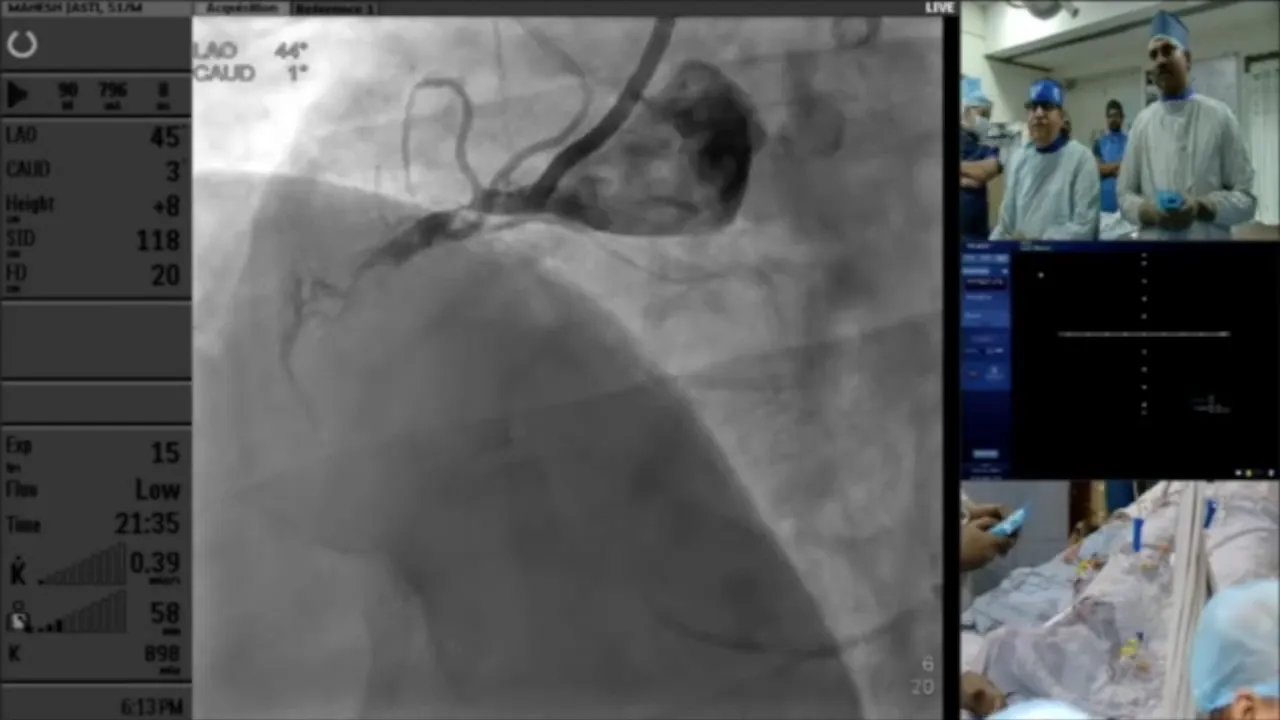

In this detailed live case presentation, Dr. Sharath Reddy walks us through a challenging coronary intervention involving a simple RCA CTO that evolved into an antegrade nonstarter. Join us as we explore the intricacies of catheter selection, wire navigation, and the decision-making process in real-time.

This case revolves around a complex coronary intervention involving a challenging RCA CTO. Initially straightforward, the situation quickly escalated into an antegrade nonstarter. Our goal is to dissect the decision-making process, focusing on catheter selection and wire navigation.

As we dive into this case, it’s crucial to grasp the anatomy and the specific challenges posed by the patient’s coronary vasculature. This understanding sets the stage for the strategic decisions made throughout the intervention.